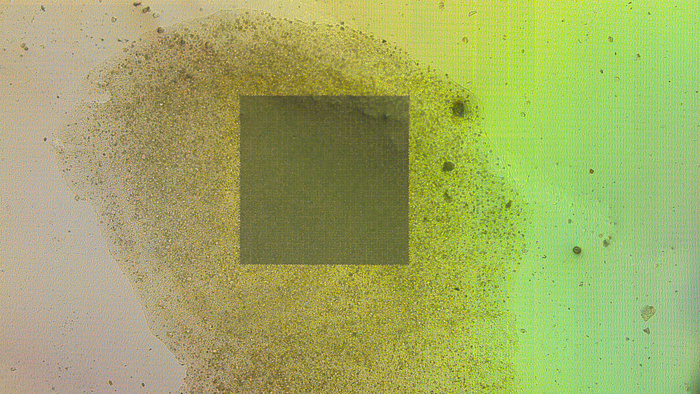

We hypothesise that stimulation of neuronal cells using light-activated photocaps promotes neuronal network formation and consequently enhances regeneration and neuroprotection after TBI. To test this hypothesis, we developed an interdisciplinary research programme that brings together specialists from the fields of neuroscience, structural biology, electrophysiology and biomedical engineering (see Figure 2). Cultured cells (Figure 3 shows a hippocampal slice culture placed on a multi-electrode array) are an invaluable tool for developing optimal stimulation parameters before shifting attention to healthy and injured brain tissue. We will investigate the optimal time window after TBI in which stimulation yields the most extensive regenerative results.

Figure 3: A hippocampal slice culture placed on a high resolution multi-electrode array with more than 4,000 recording sites and an interelectrode distance of 32 micrometres.